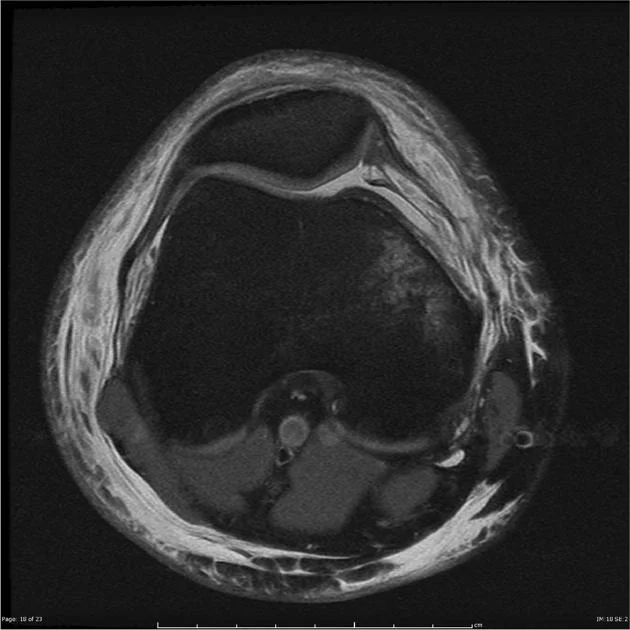

Imaging is used to confirm the diagnosis, assess soft tissue damage, and evaluate the shape and alignment of your knee structures.

MRI (Magnetic Resonance Imaging)